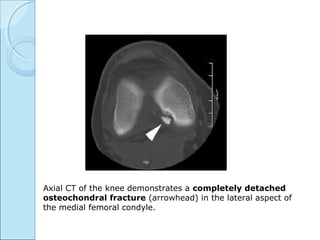

 CT FINDINGS

Usually axial cuts.

For cortical defects & loose bodies.

Island of bone demarcated by rare field zone.

Axial CT of the knee demonstrates a completely detached

osteochondral fracture (arrowhead) in the lateral aspect of

the medial femoral condyle.